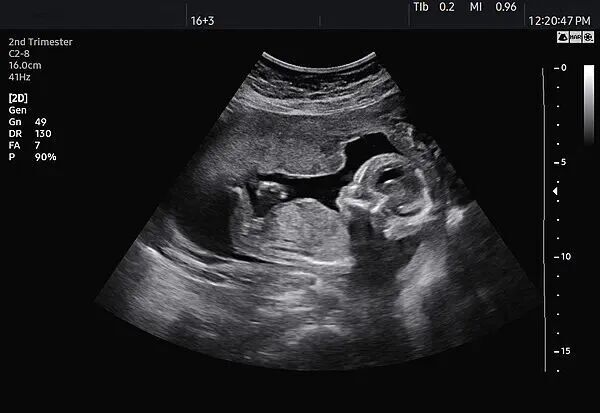

与此同时,该店使用B超机的行为也可能涉嫌违法。《关于严禁非法使用超声诊断仪开展“胎儿摄影”活动的通知》规定,根据《医疗器械分类目录》规定,超声诊断仪属于第二类、第三类医疗器械,适用范围为医疗机构临床诊断。非医疗机构不得使用超声诊断仪。该店并非医疗机构,使用的超声诊断仪来源不明、质量不明,操作设备的工作人员是否有资质、操作是否规范同样不明,可能会对孕妇和胎儿的健康产生一定影响。